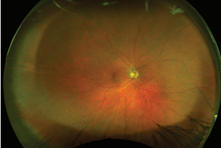

Retinal photographs allow us to look at the surface of the retina, which looks like this: